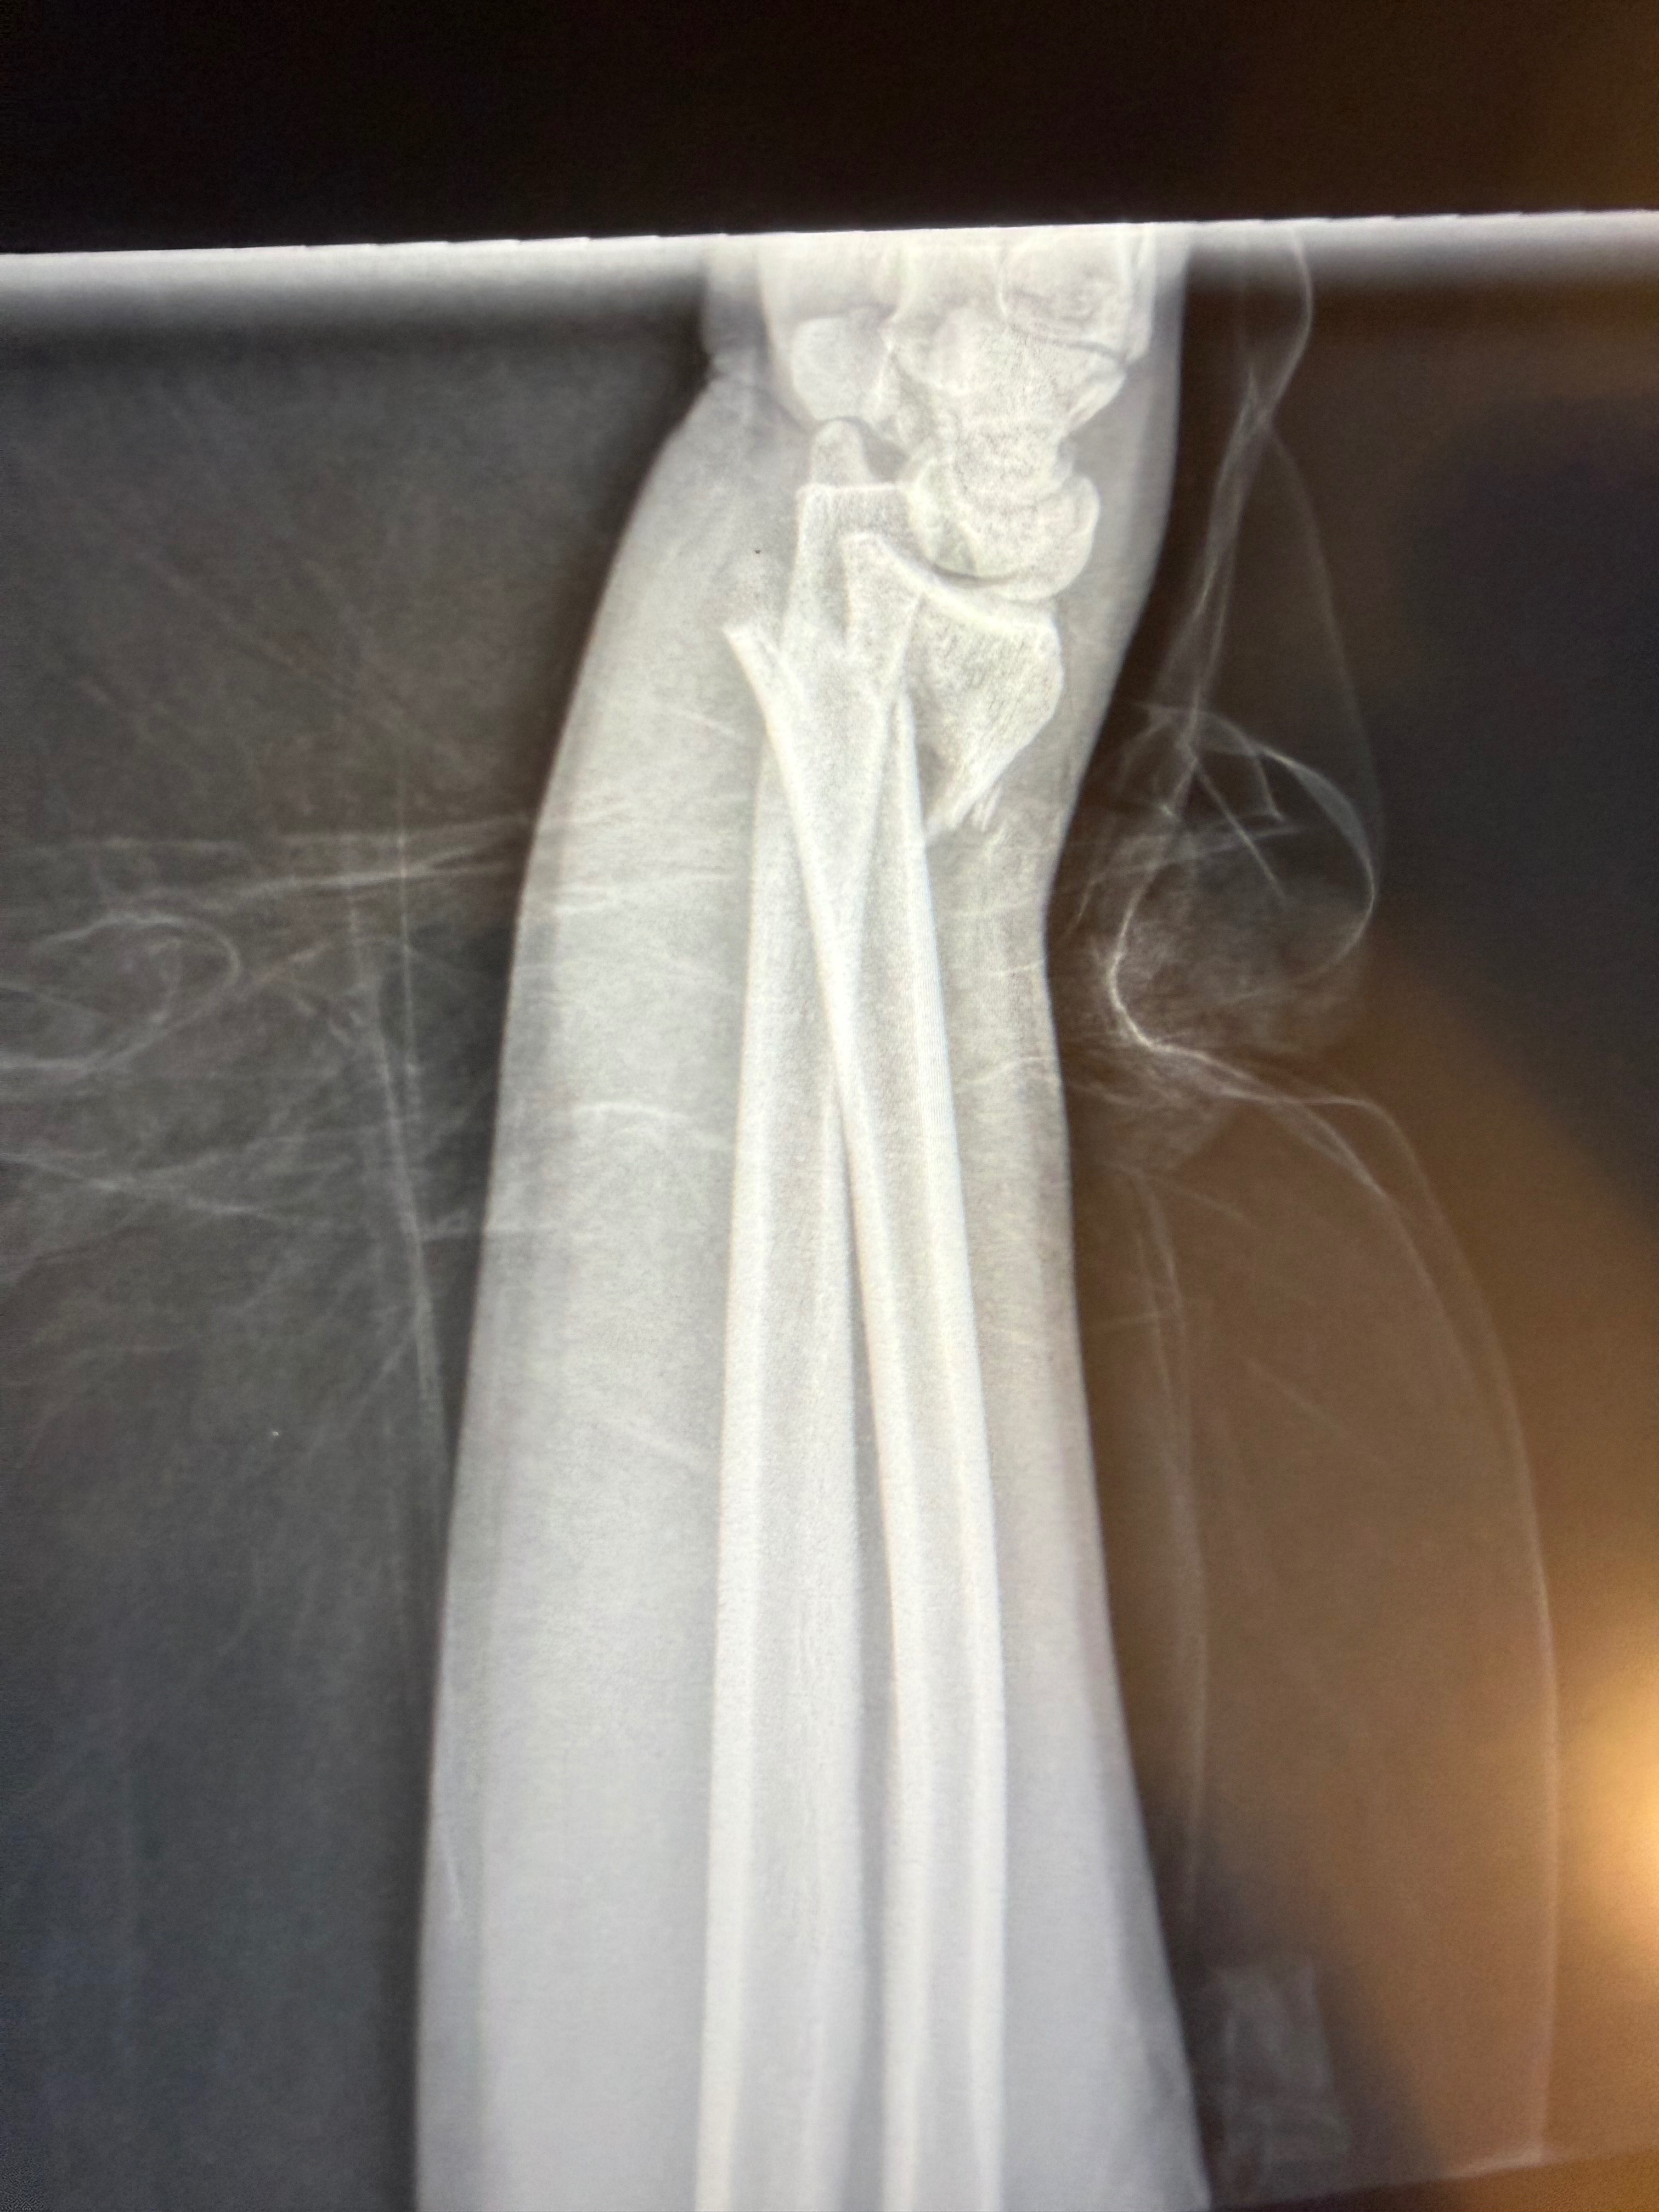

Sam sustained a broken wrist that required immediate surgery with a plate and screws, stitches in her lower abdomen, and torn muscles in her left hip, making it extremely painful and difficult for her to walk.